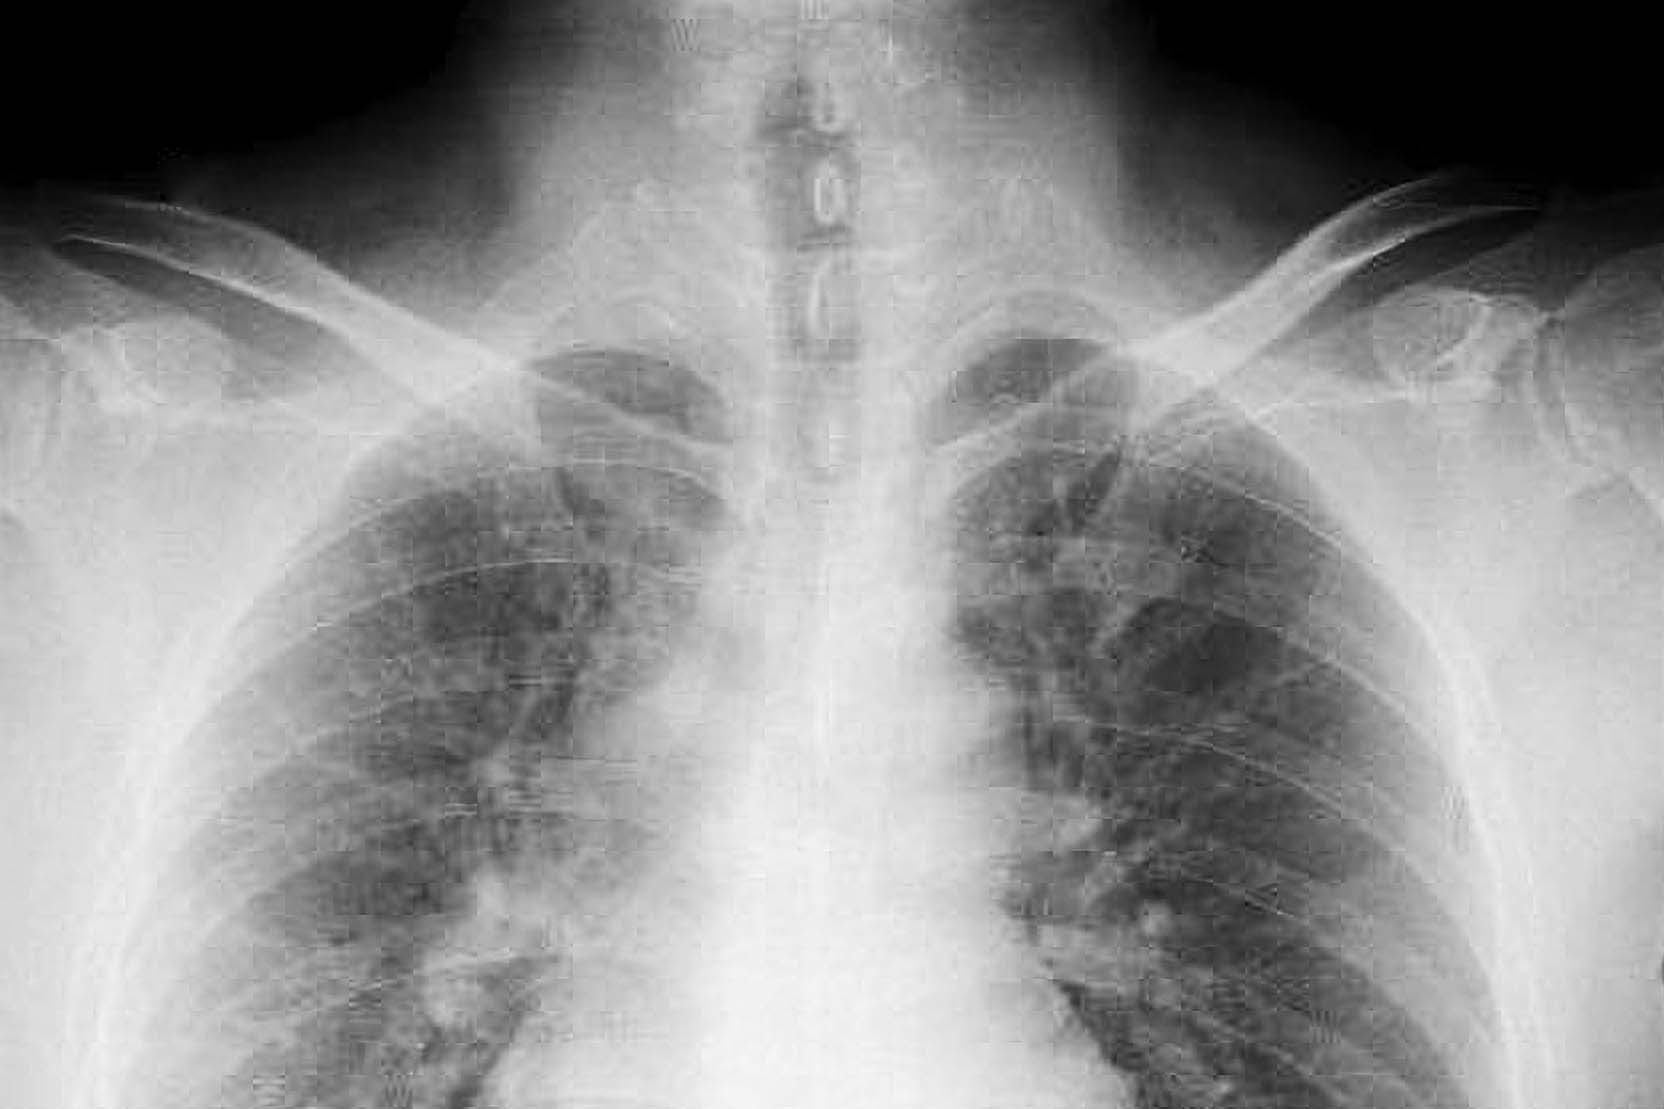

據《每日鏡報》報導,現年57歲的詹姆斯(Heather Von St James)表示,小時候在寒冷夜晚會穿上父親從工地帶回的外套外出餵寵物兔,當時並不清楚外套上的灰白粉塵其實含有石棉。直到36歲懷孕期間,她出現長期疲倦與發燒等症狀,就醫後透過電腦斷層檢查發現肺部有腫瘤,最終確診為胸膜間皮瘤(pleural mesothelioma),是一種由接觸石棉引起的侵襲性肺癌。